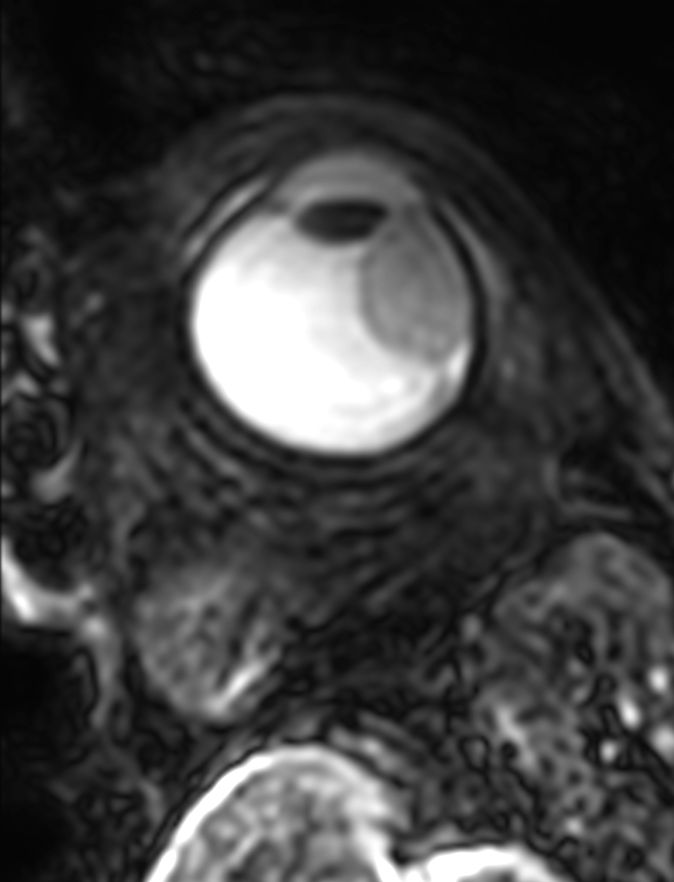

Perfusion and diffusion scans are used for differential diagnosis. The diffusion sequence can help a radiologist confirm whether a tumor is malignant or not and the perfusion results can show the effects of treatment. Using ultrasound to evaluate the effects of treatment takes longer due to post-treatment inflammation.